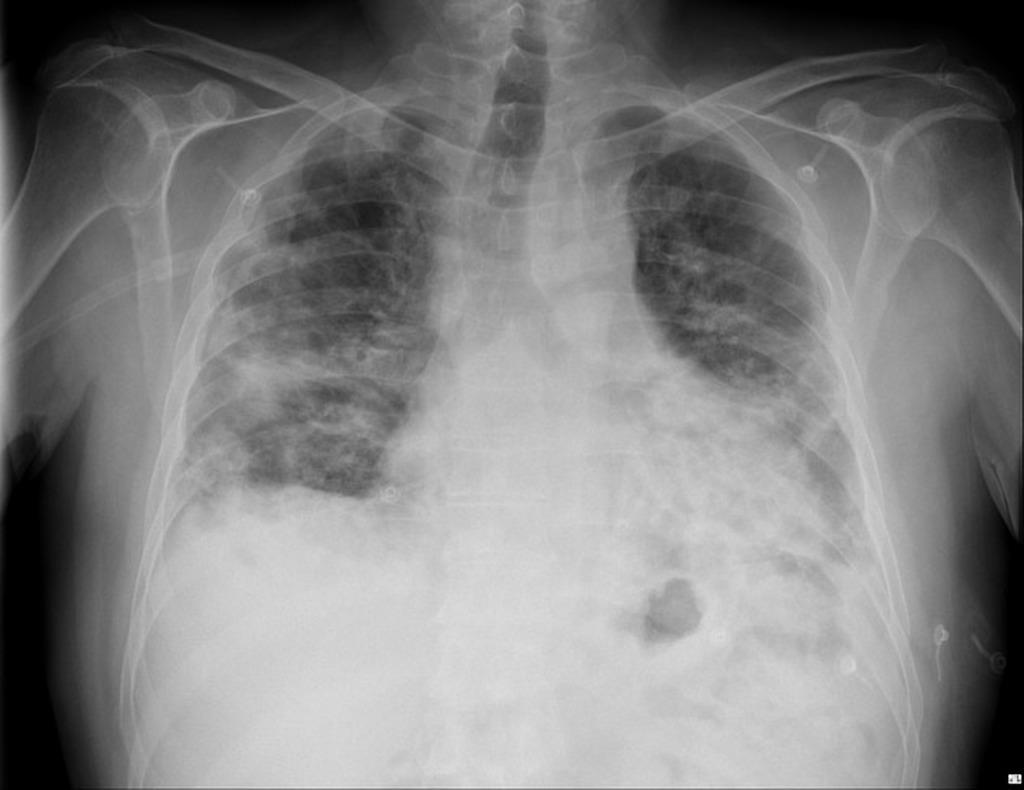

Chest X Ray Organizing Pneumonia . Organizing pneumonia (op), characterized histopathologically by patchy filling of alveoli and bronchioles by loose plugs of. Initial management included broad spectrum antibiotics. Diagnosis of cryptogenic organizing pneumonia requires imaging tests and, if the diagnosis is not otherwise clear, lung biopsy. Organizing pneumonia comprises a histological pattern characterized by granulation tissue polyps within alveolar ducts and alveoli. Organizing pneumonia is an idiopathic form of organizing pneumonia also known as collagenized organizing pneumonia, cicatricial variant of organizing pneumonia, fibrosing organizing. Organizing pneumonia (op) is an inflammatory disorder involving both the peripheral bronchioles and alveoli simultaneously. A peripheral distribution similar to chronic eosinophilic pneumonia may occur. In the context of interstitial pneumonia, the organizing pneumonia (op) pattern (opp) refers to the histologic finding of polypoid plugs of loose connective tissue in distal.